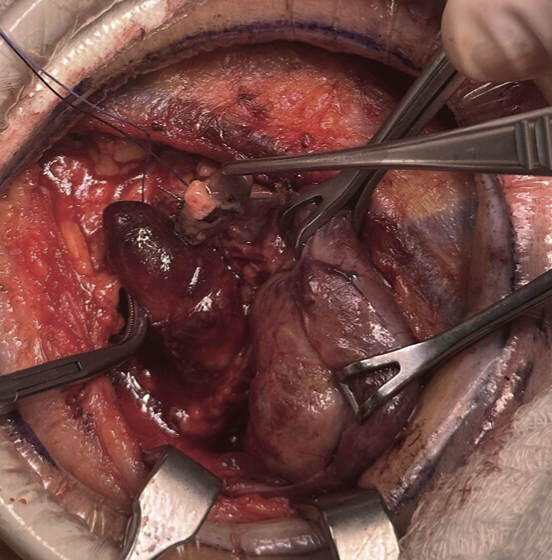

Julián Andrés Díaz Santamaría, Marco Tulio Gonzalez, Arnaldo Almendros Mello

|

|

|